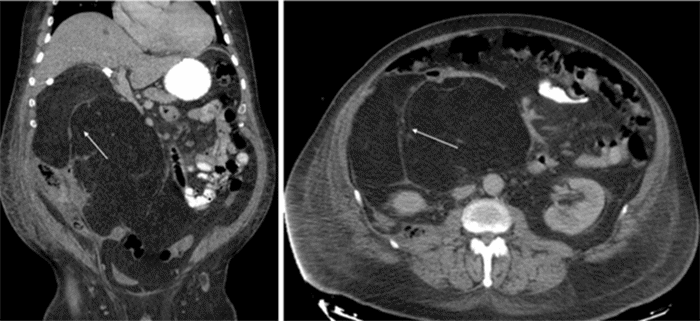

Seven months after the initial presentation, a repeat abdominal and pelvic CT scan revealed significant enlargement of the fatty retroperitoneal mass (20.2 × 28.2 × 14.1 cm) with mass effect on surrounding organs (right kidney, duodenum, colon, liver, inferior vena cava, and pancreas). (Figure 3). Thin internal septations were apparent. Due to rapid tumor growth, significant mass effect, and delays in resection due to post-cholecystectomy complications, the decision was made to proceed with surgical resection without further biopsy. Nine months after initial imaging diagnosis, he was deemed an acceptable surgical risk.

Figure 3. CT Imaging Demonstrates Preoperative Mass Effect. Published with Permission

Small arrow: Denotes the mass significantly impacting adjacent bowel loops. Large arrow: Denotes the mass causing substantial compression of the inferior vena cava

Imaging diagnosis of PLH is challenging due to its similarity to other lipomatous tumors. However, recent case series, after reviewing all reported cases, suggest some findings that may aid in diagnosis. Most PLHs are well-demarcated cystic and solid lesions exhibiting progressive or late enhancement on contrast-enhanced CT or MRI. They are most frequently located in the pancreatic head or uncinate process. MRI can demonstrate the solid component as iso- to low-intensity on T1-weighted images and iso- to high-intensity on T2-weighted images.¹˒³ FDG-PET demonstrates uptake in approximately 20% of patients, potentially leading to misdiagnosis as pancreatic adenocarcinoma.³ Many of these lesions remain stable over time on serial imaging, unlike the rapid growth observed in our patient.³ Our patient’s MRCP revealed multiple irregular nodular soft tissue densities with increased T2WI signal. Contrast-enhanced CT showed multiple internal septae without progressive or late enhancement but did reveal increased vascularity. The large size of our patient’s mass caused significant mass effect on surrounding organs and vascular structures, making it difficult to assess invasion, a feature distinguishing this case from others.